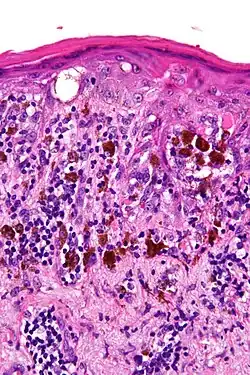

Light microscopy of lentigo maligna showing the characteristic atypical epidermal melanocytes. H&E stain. -